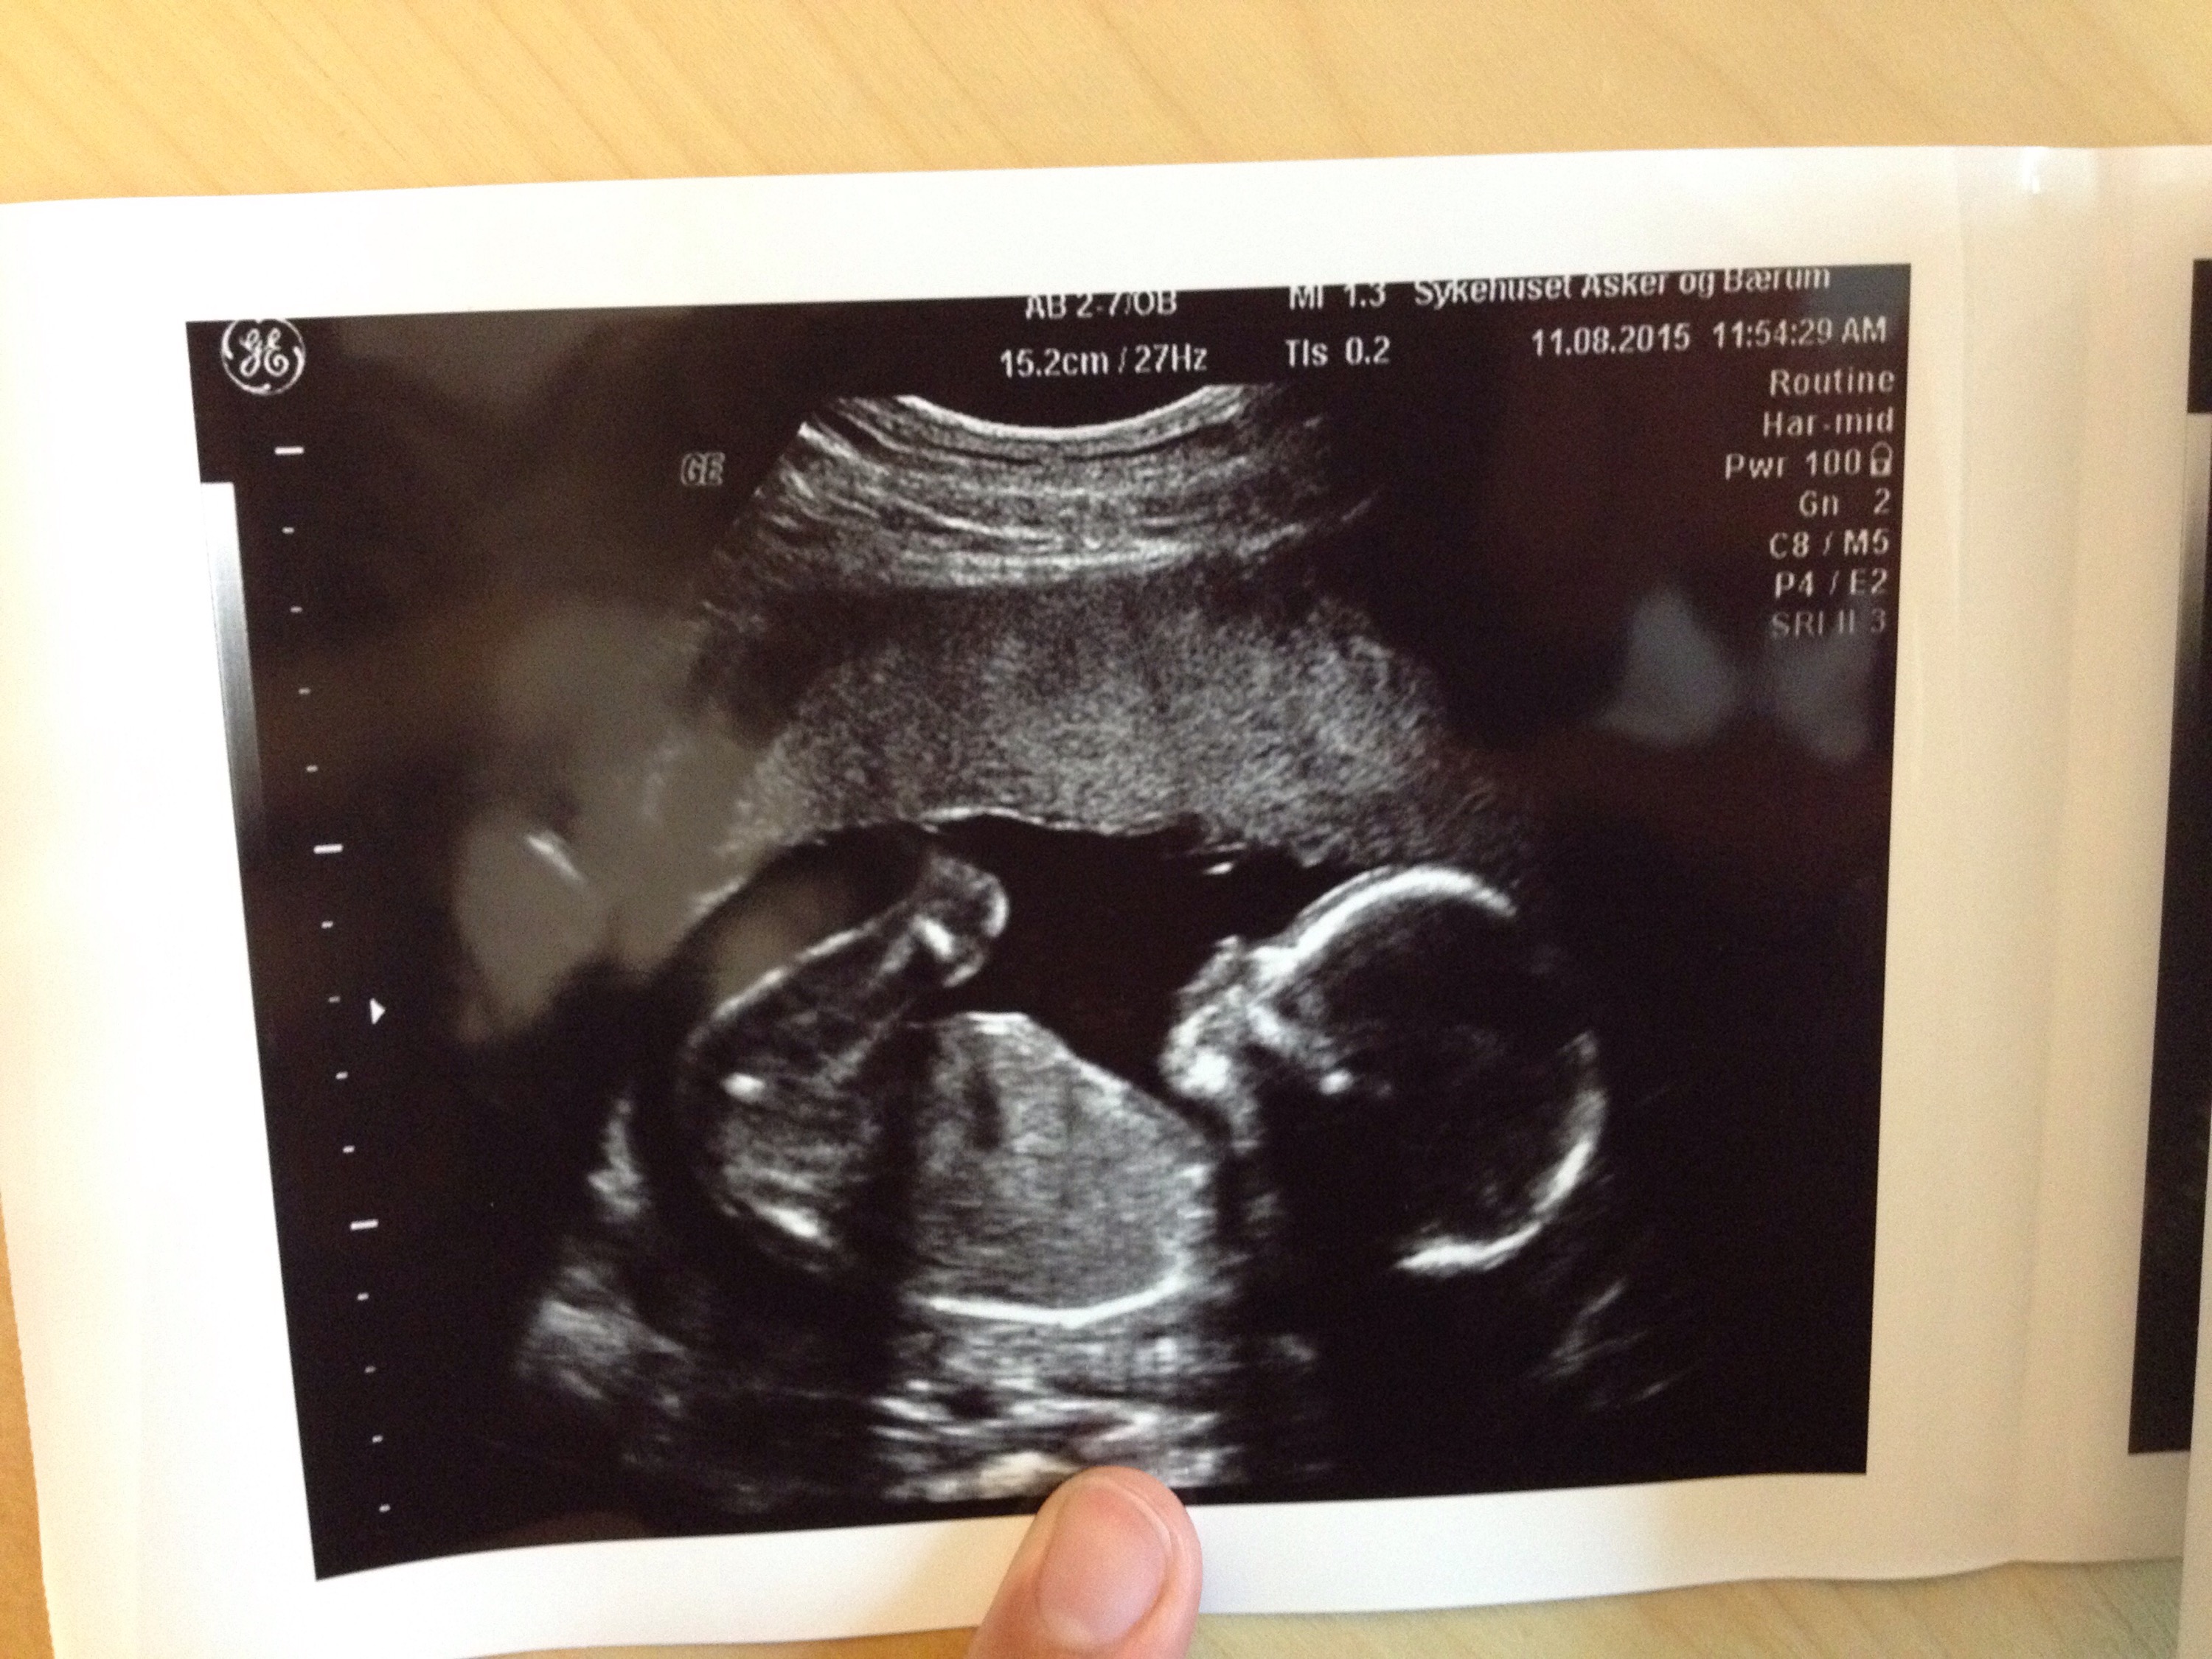

Idag har vi varit på ultraljud, så häftigt ju. Tänk att den här lilla parveln växer i mig. Hen är inte lång, typ 12cm från huvud till rumpa och lårbenet är 3cm, tur att hen har ett tag på sig att växa till sig. Vi fick nytt datum med så det är den 3 januari som gäller nu. Snart bara hälften kvar.